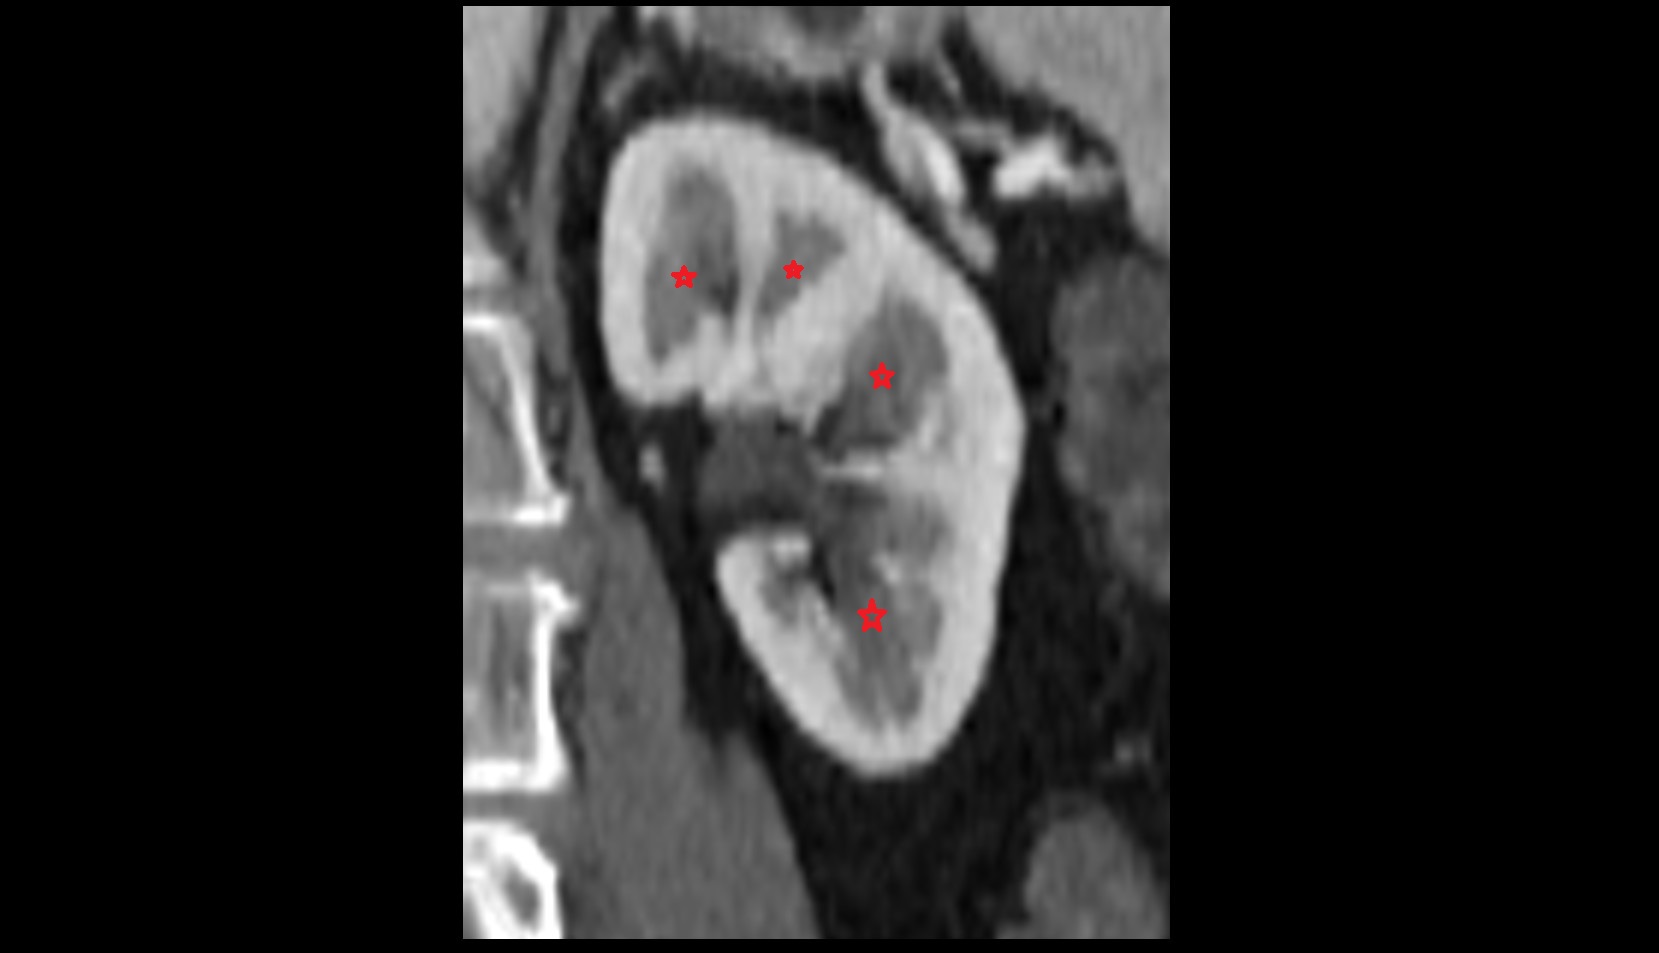

- kidneys

- Right kidney

- Left kidney

- Kidney cortex (Renal cortex)

- Renal capsule

- Renal medulla

- Renal pyramids